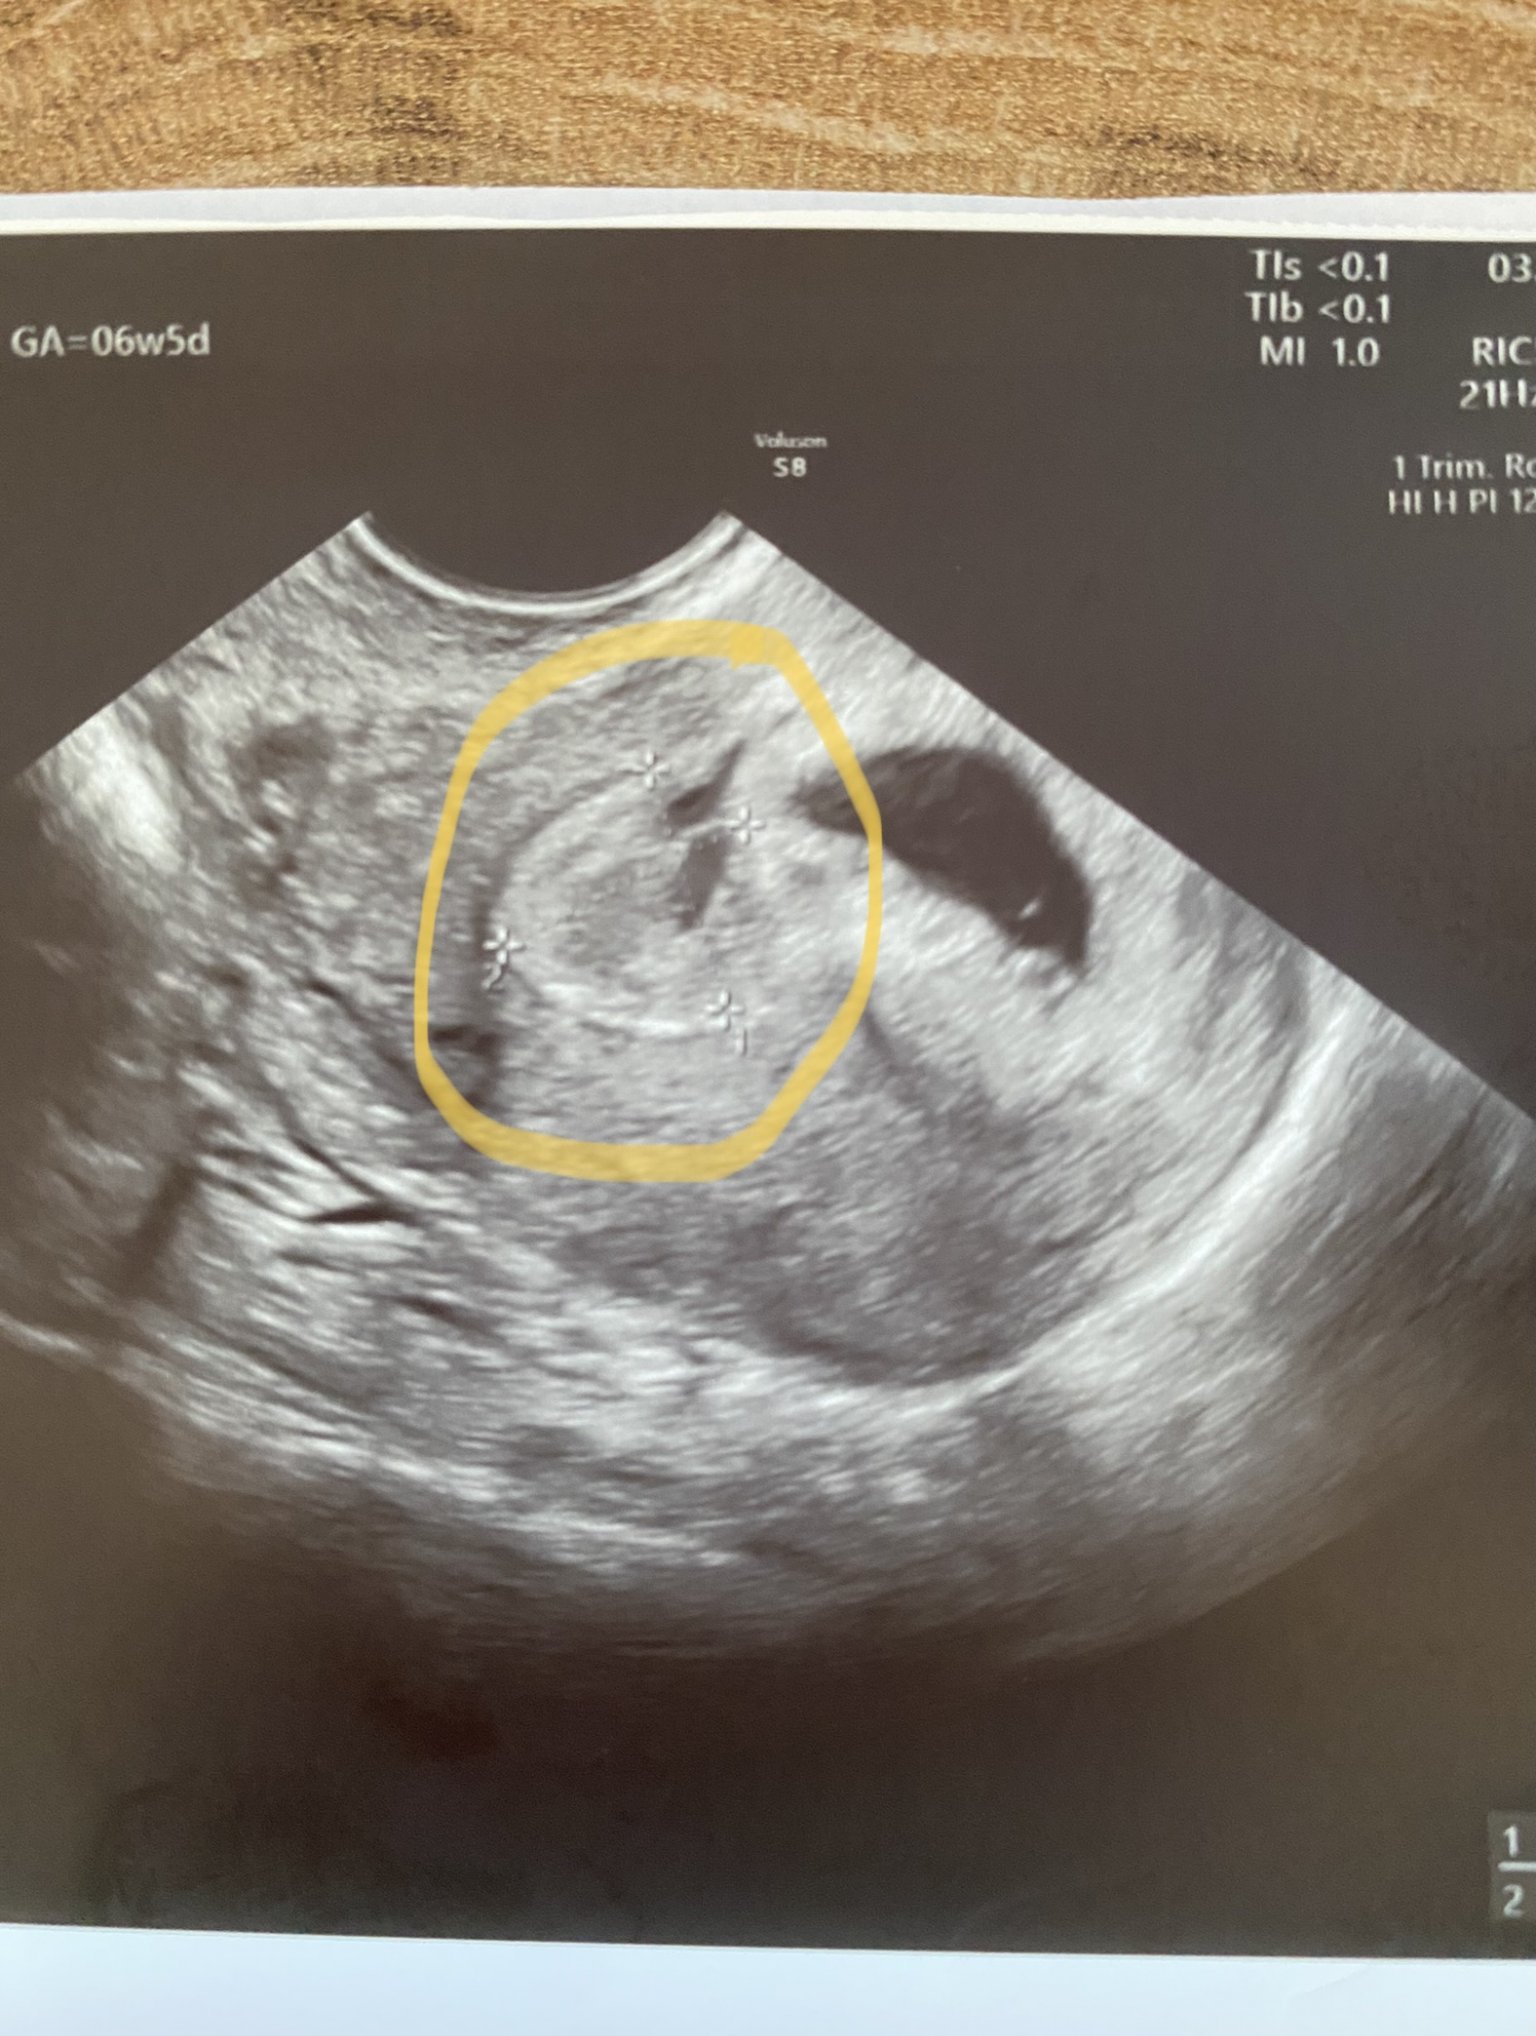

За първи път се включвам, първа бременност, инвитро. Според датата на цикъла трябва да съм в 7+1, но според датата на трансфера съм по-скоро 6+6.